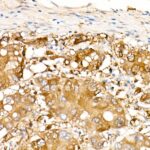

Immunohistochemistry analysis of paraffin-embedded human liver cancer using ALDH1A1 Rabbit mAb (A22351) at dilution of 1:400 (40x lens).Perform high pressure antigen retrieval with 10 mM citrate buffer pH 6.0 before commencing with IHC staining protocol.